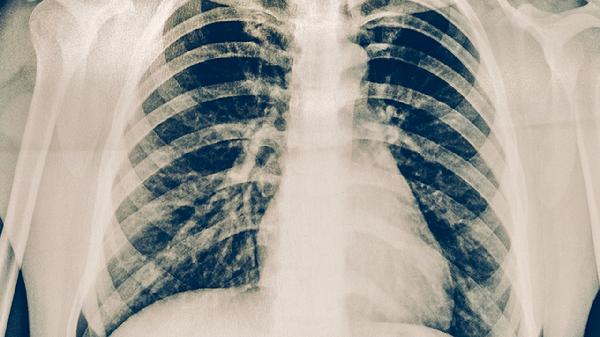

預(yù)防肺結(jié)核傳播需注重室內(nèi)通風(fēng)換氣,與咳嗽患者保持1米以上距離,必要時佩戴醫(yī)用防護(hù)口罩?;顒有苑谓Y(jié)核患者應(yīng)單獨居住一室,痰液需用含氯消毒劑處理,餐具需煮沸消毒。密切接觸者應(yīng)進(jìn)行結(jié)核菌素試驗或γ-干擾素釋放試驗篩查。兒童、老年人、糖尿病患者等免疫力低下人群可考慮接種卡介苗。出現(xiàn)持續(xù)兩周以上的咳嗽、咳痰、午后低熱、夜間盜汗等癥狀時,應(yīng)及時到呼吸內(nèi)科或感染科就診,通過痰涂片檢查、胸部X線等明確診斷。